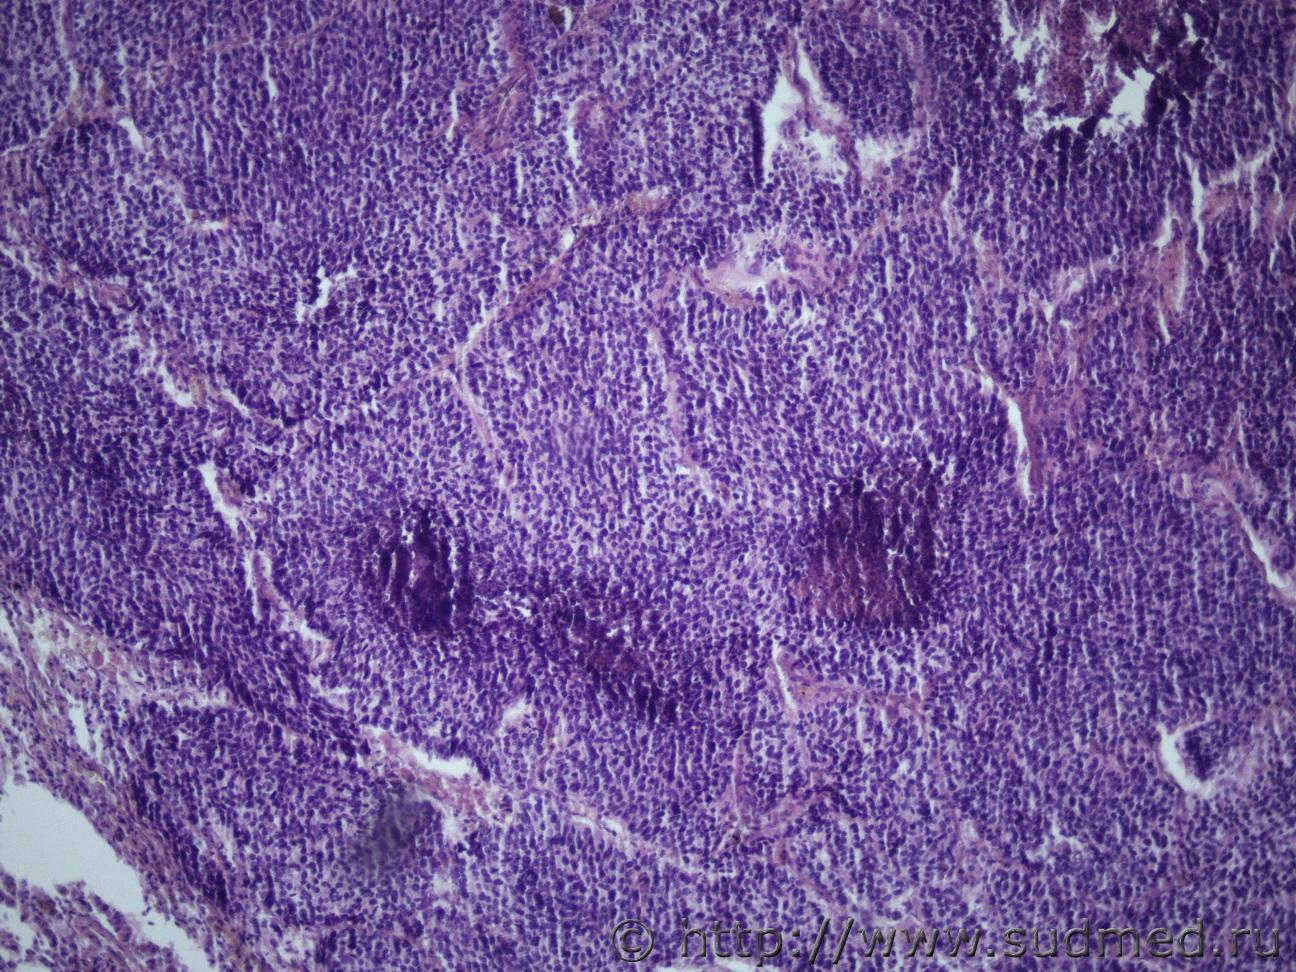

Ув. коллеги, еще опухоль корня легкого. Муж 1957 года рожденияСудебная медицина - Прикрепленное изображение Судебная медицина - Прикрепленное изображениеСудебная медицина - Прикрепленное изображениеСудебная медицина - Прикрепленное изображение

Плоскоклеточный низкодифференцированный рак.